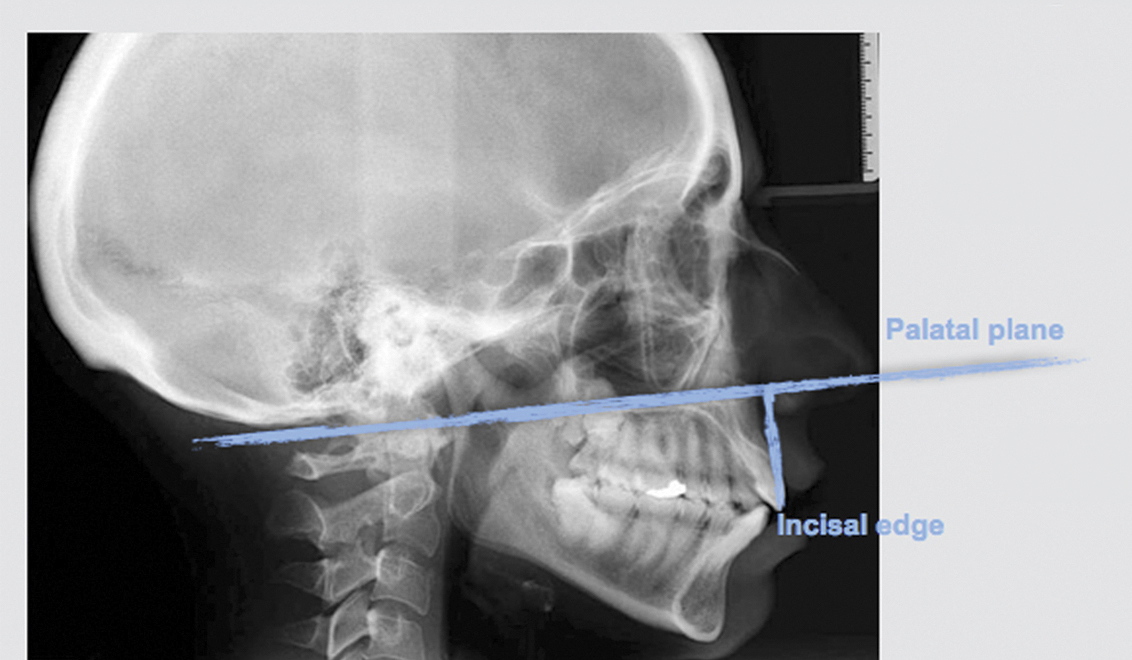

Defining the proportions between the facial thirds of the face in frontal and lateral views will identify any alterations needed in the middle or inferior facial thirds. An increase in ratio of the middle third may indicate vertical maxillary excess (VME).6 Clinical assessment of the facial thirds is only approximative, and further radiographic imaging may be required (Figure 4). VME can be identified using a cephalometric analysis by localizing the distance between the incisal margins of the central incisors and the anterior nasal spine-posterior nasal spine (SPA-SPP) plane (palatal plane-incisal edge: 29 mm to 31 mm).7,11 However, the authors consider the cephalometric measurement—“palatal plane-incisal edge”—unreliable because the distance may vary depending on the amount of wear or in overeruption cases. Therefore, the authors suggest measuring the distance from the palatal plane to the cemento-enamel junction (CEJ) to eliminate any misleading data that might result from the presence of incisal wear, taking into consideration whether an altered CEJ position has resulted from compensatory overeruption.

Fig 4. Lateral radiograph of patient with VME (anterior maxillary height: palatal plane-incisal edge = 29 mm to 31 mm).

Figure 4